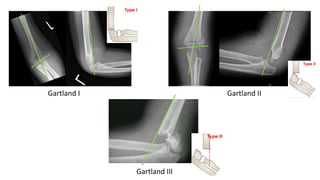

Gartland’s classification

I Non-displaced fracture

Anterior humeral line ✓

Baumann’s angle ✓

II

Displaced, intact

posterior cortex

Anterior humeral line ✘

Baumann’s angle +/-

III Totally displaced

Baumann’s angle ✘

Gartland I Gartland II

Gartland III

Gartland’s classification I Non-displacedfracture Anterior humeral line ✓ Baumann’s angle ✓ II Displaced, intact posterior cortex Anterior humeral line ✘ Baumann’s angle +/- III Totally displaced Anterior humeral line ✘ Baumann’s angle ✘

Gartland I GartlandII Gartland III